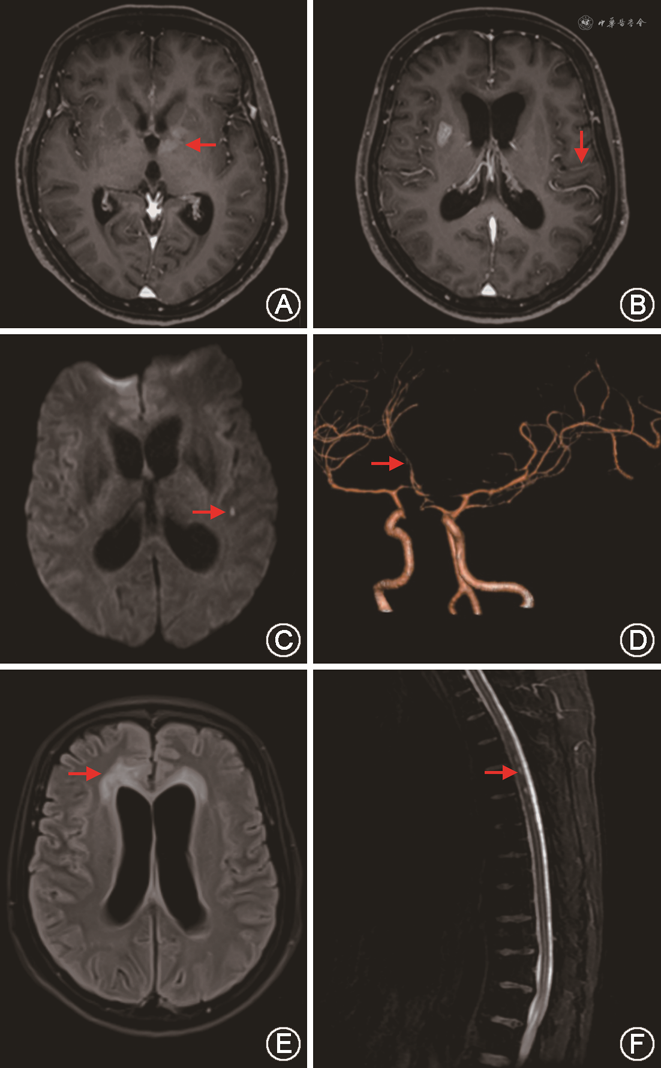

胸部X线或胸部CT检查可提示存在活动性或陈旧性结核感染证据。头颅CT、MRI增强扫描可显示颅底基底池、外侧裂及脑干周围脑膜呈不规则条状、结节状强化[9]。脑实质内可见散在的粟粒状等密度或稍高密度小结节。脑内结核瘤增强扫描可见环形、靶形或不规则的团块阴影。早期可见脑室缩小等脑水肿征象,晚期可见脑室普遍性扩大等脑积水征象。头颅MRI DWI可显示合并脑梗死的影像学改变[9]。头颅CTA、MRA可显示颈内动脉远端及大脑前、中动脉近端血管狭窄。见图1。